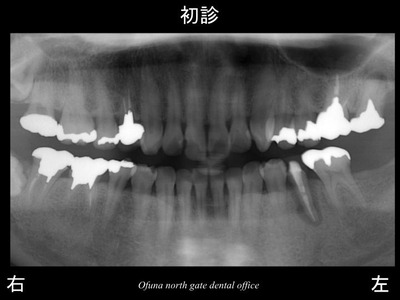

以下は初診時です。

下顎左側の奥から2番目の歯が腫れているとのことで来院された患者様です。

診査の結果、歯根破折 と診断されました。

先週の症例も歯根破折 でしたが、本当によくあることなのです。

以下が初診時のレントゲンです。

先ほどの症例と同様に歯根破折 していました。

以下が初診時です。

下顎左側の奥から2番目の歯の被せ物が取れたとのことで来院されました。

歯肉の中までおよぶ深い虫歯となっていました。

虫歯となっている歯の手前は、だいぶ前に抜歯されたそうです。